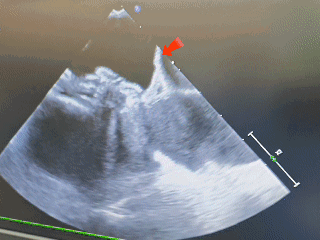

经食道超声可见

第一个缺损8.06mm

第二个缺损5.63mm

术中超声:术中经食道超声可见有两个缺损,分别为8.06mm、5.63mm,和术前超声报告对比有所偏差,两缺损距离约8.48mm。